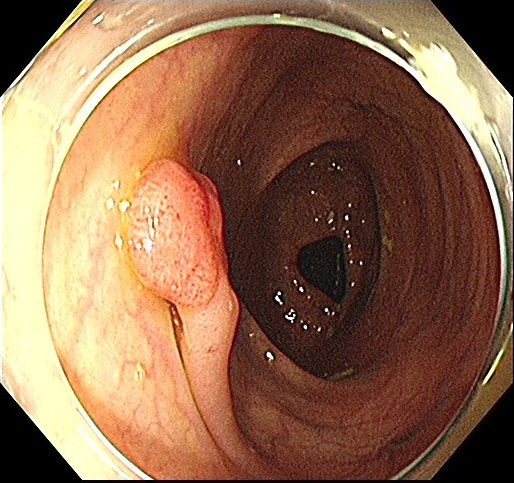

General objects for detection task such as car, pedestrian or table which have defined outline or appearance which offers strong cues for neural network to learn. Polyps, on the other hand, have various sizes which scales from diminutive(<5mmabsent5𝑚𝑚<5mm) to giant(>30mmabsent30𝑚𝑚>30mm) Shussman2014 and present different appearances such as sessile or pedunculated,1. This makes detecting polyps using a general-purpose oriented network more difficult and urges us to design a object-specific detector.

(b) pedunculated

Figure 1: Examples of possible polyp category within a frame: (a) sessile, (b) pedunculated or (c) multiple of them.